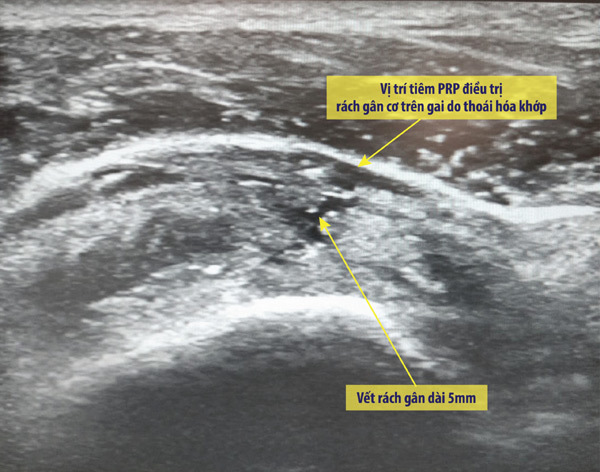

Điểm đặc biệt là các ca tiêm PRP điều trị viêm khớp tại Bệnh viện Vinmec đều diễn ra dưới hướng dẫn của máy siêu âm để xác định trúng vị trí cần tiêm.

Theo BS Nhung cho biết: “Tiêm chế phẩm PRP nhằm tác động trực tiếp vào tổn thương nên việc xác định đúng vị trí cần tiêm là rất quan trọng. Dưới hướng dẫn của máy siêu âm GE Healthcare S9 hiện đại có đầu dò phẳng, tần số cao, độ phân giải HD cho hình ảnh rõ nét, êkip gồm bác sĩ cơ xương khớp và bác sĩ chẩn đoán hình ảnh có thể tìm được vị trí chính xác gây thoái hóa khớp vai và tiêm trực tiếp vào vị trí đó”.

| Hình ảnh tiêm PRP dưới hướng dẫn siêu âm điều trị viêm khớp vai |

Trên thực tế, mức độ khỏi và dứt điểm bệnh lâu dài sẽ phụ thuộc rất lớn vào chất lượng chế phẩm PRP sau tách chiết và việc tiêm đúng chuẩn vào vị trí tổn thương. Do đó, quy trình điều chế PRP tại Vinmec được thực hiện với giám sát chặt chẽ trong labo đạt chuẩn quốc tế. Việc tiêm PRP dưới hướng dẫn siêu âm có khả năng tạo sự khác biệt trong hiệu quả điều trị nhờ tác động trực tiếp và chính xác vào vị trí tổn thương.